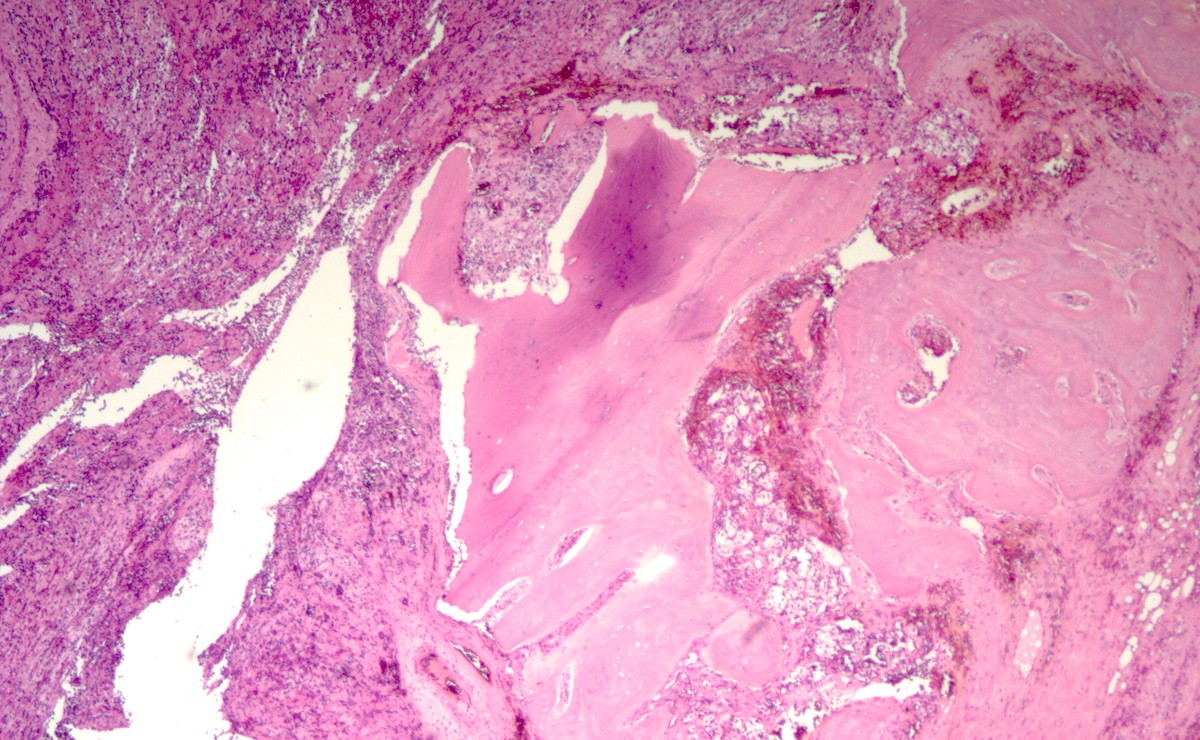

Microscopic (histologic) description

- Prevailing histologic pattern: epithelioid chief cells arranged in distinctive clusters / nests (zellballen pattern), separated by prominent fibrovascular stroma (J Clin Med 2018;7:280)

- Trabecular pattern: ribbons or cords of epithelioid cells divided by fibrous bands

- Other patterns: pseudorosette, angioma-like, spindled and sclerosing

- Chief cells: round, oval to polygonal cells with abundant granular basophilic, eosinophilic or amphophilic cytoplasm (Surg Pathol Clin 2019;12:951)

- May have dysmorphic vessels, melanin-like pigment (neuromelanin) (pigmented paraganglioma), amyloid, abundant stroma and osseous metaplasia (Diagn Pathol 2012;7:77, Hum Pathol 1992;23:33)

- Necrosis is unusual except in patients who have undergone preoperative tumor embolization

Microscopic (histologic) images

Contributed by Luvy Delfin, M.D. and Sylvia L. Asa, M.D., Ph.D.